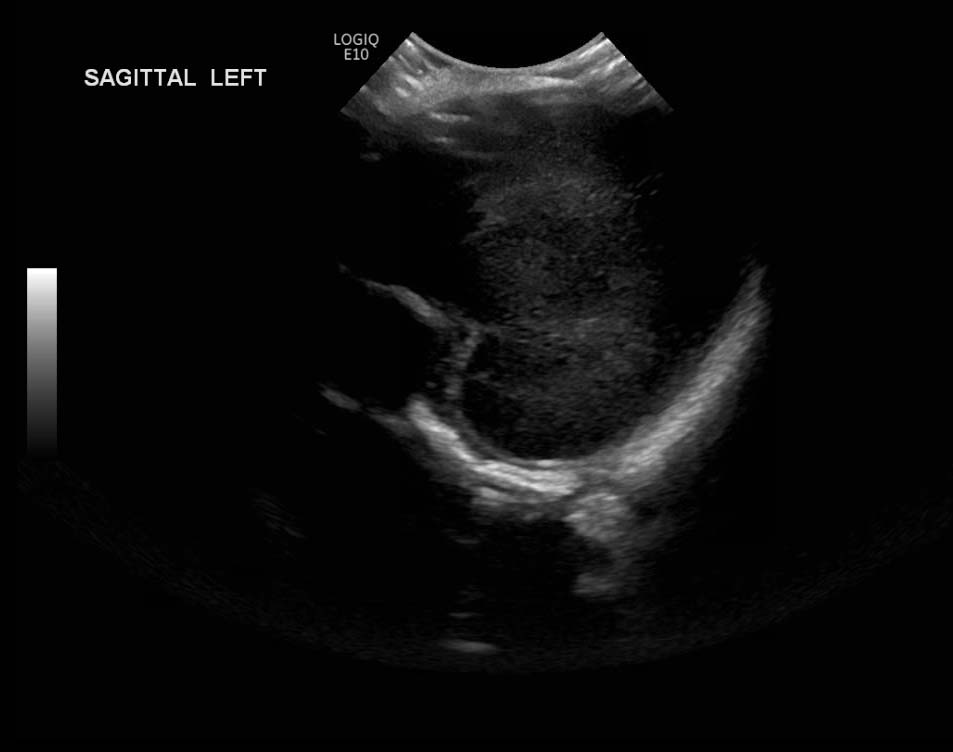

Age: 4 days (born at 24 weeks)

Sex: Male

Indication: Evaluate for germinal matrix hemorrhage

Grade 2 germinal matrix hemorrhage

Sample ReportLeft germinal matrix hemorrhage involving the caudothalamic groove and layering in the occipital horn of the left lateral ventricle without hydrocephalus (grade 2).

No abnormal brain parenchymal echogenicity or extra-axial collections.

Premature sulcation pattern.